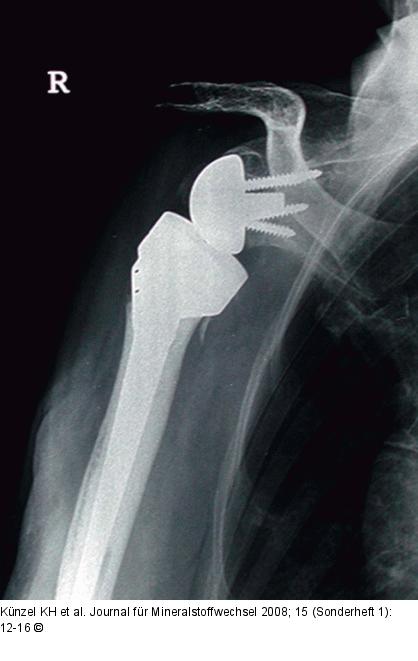

Abbildung 3: Prothese Inverse Prothese |